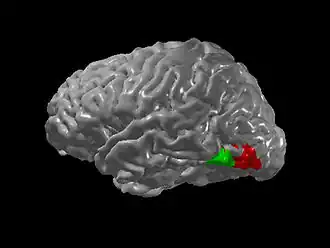

Regiunile dedicate ale creierului sunt specializate pentru anumite funcții. Comunicarea crescută între regiuni specializate pentru diferite funcții poate explica numeroasele tipuri de sinestezie. De exemplu, experiența auditivă de a vedea culoarea (sau culori) atunci când subiectul se uită la grafeme s-ar putea datora activării încrucișate a zonei de recunoaștere a grafemelor și a zonei de culoare numită V4 (vezi figura).[14]

Acest lucru este susținut de faptul că sinestezii grafem-culoare pot identifica culoarea unui grafem în vederea lor periferică chiar și atunci când nu pot identifica în mod conștient forma grafemelui.[14]